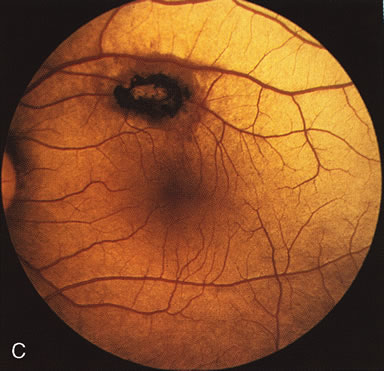

HEREDITARY HEMORRHAGIC MACULAR DYSTROPHY (PSEUDOINFLAMMATORY MACULAR DYSTROPHY OF SORSBY)

FA plays an important role in the understanding of this rare disorder. In the earliest manifestations of the disease, FA shows a single, isolated choroidal neovascular membrane unassociated with other causes of a membrane, such as drusen or angioid streaks (Fig. 13).25 Presumably this membrane is the cause of the subsequent hemorrhagic maculopathy with secondary disciform scarring, occurring initially in the macula but often extending throughout the retina.

Fig. 13. Hereditary hemorrhagic macular dystrophy (pseudoinflammatory macular dystrophy of Sorsby). Fluorescein angiography in this family member demonstrates that the earliest finding is an isolated choroidal neovascular membrane B). Despite laser photocoagulation, a hemorrhagic maculopathy developed in this eye (C, D) and eventually a disciform scar (E) formed, as it had in the fellow eye, and in the eyes of other affected family members.

Abnormal choroidal perfusion, manifested on FA as a delay in choriocapillaris filling, has been seen in the restudy of some of Sorsby's initial pedigrees.26 This unusual pattern has been related to the histopathologic finding of a “confluent, lipid-containing, amorphous deposit found between the basement membrane of the RPE and the inner collagenous layer of Bruch's membrane.”27